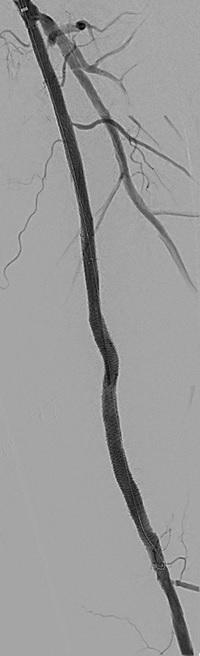

1. CTO of the left superficial femoral artery in a male patient suffering from severe claudication in the left calf

2. After subintimal passage, it was impossible to redirect the guidewire into the patent lumen distal to the CTO

3. Positioning of the BeBack catheter to re-enter the guidewire. Arrow indicates an orientation-marker

4. Marker appearing as a “C” indicates the direction of the needle, with the needle protruding maximally out of the BeBack catheter

5. An 0.018” guidewire passing into the patent distal lumen

6. Result after stenting